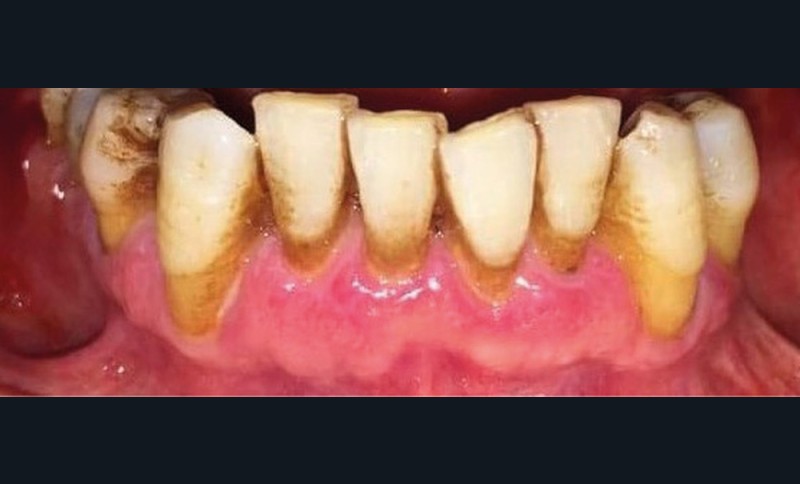

À l’interrogatoire, le patient affirme qu’il a des difficultés à maintenir une hygiène bucco-dentaire satisfaisante du fait des douleurs, et n’a pas pu consulter son chirurgien-dentiste pour son détartrage annuel en raison de la crise sanitaire en cours. L’examen clinique révèle une parodontite chronique (stade 3) généralisée et des lésions jugales (fig. 1 et 2), labiales (fig. 3) et gingivales (fig. 4) érythémateuses et kératosiques. Les lésions kératosiques jugales sont de type réticulé (fig. 1 et 2) ; les lésions kératosiques labiales sont associées à de petites érosions (fig. 3) ; les lésions palatines à des ulcérations (fig. 5). La langue présente une lésion blanche en « tache de bougie » (fig. 6) ; la muqueuse du plancher buccale est saine (fig. 7). Le signe de la pince est négatif. Le patient n’est pas porteur de prothèse dentaire malgré un édentement de moyenne étendue. Aucune lésion cutanée ou génitale n’est rapportée par le patient.